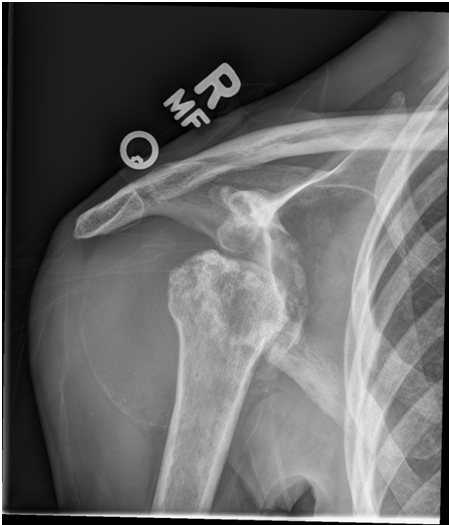

Conventional Radiography

All radiography is now performed using either computed radiography or digital radiography at eight of our ten clinical sites. We perform close to 100,000 adult non-emergency room studies every year, representing radiographic examinations of the axial and appendicular skeleton and including all radiographic studies of the head and neck.